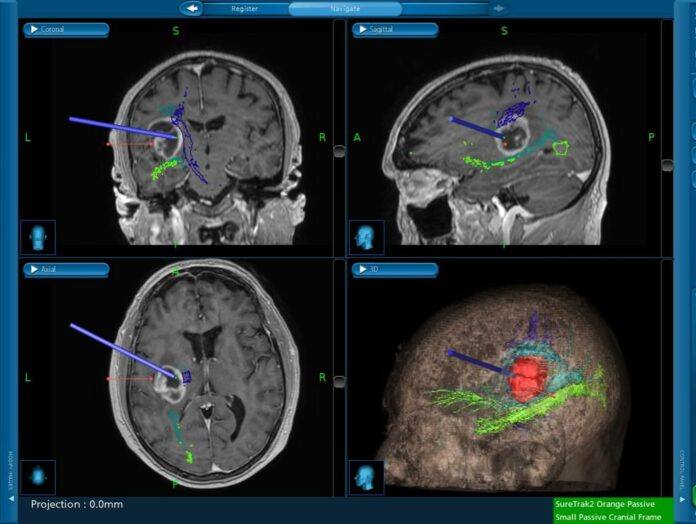

Tale esame, chiamato “Trattografia”, è stato poi importato su un sistema di “Neuro-Navigazione” (modello Stealthstation S7 di marca Medtronic, famosa azienda americana del settore, in dotazione all’ospedale) che ha guidato i chirurghi durante l’atto chirurgico al fine di poter rimuovere tutto il tumore evitando le zone del cervello che svolgono una funzione particolarmente importante (come parlare).

Lo studio funzionale del cervello è stato, poi, ripetuto dopo l’intervento chirurgico e, comparato col precedente, ha permesso di verificare non solo che il tumore è stato del tutto rimosso ma, altresì, che nessun deficit permanente è rimasto al paziente.